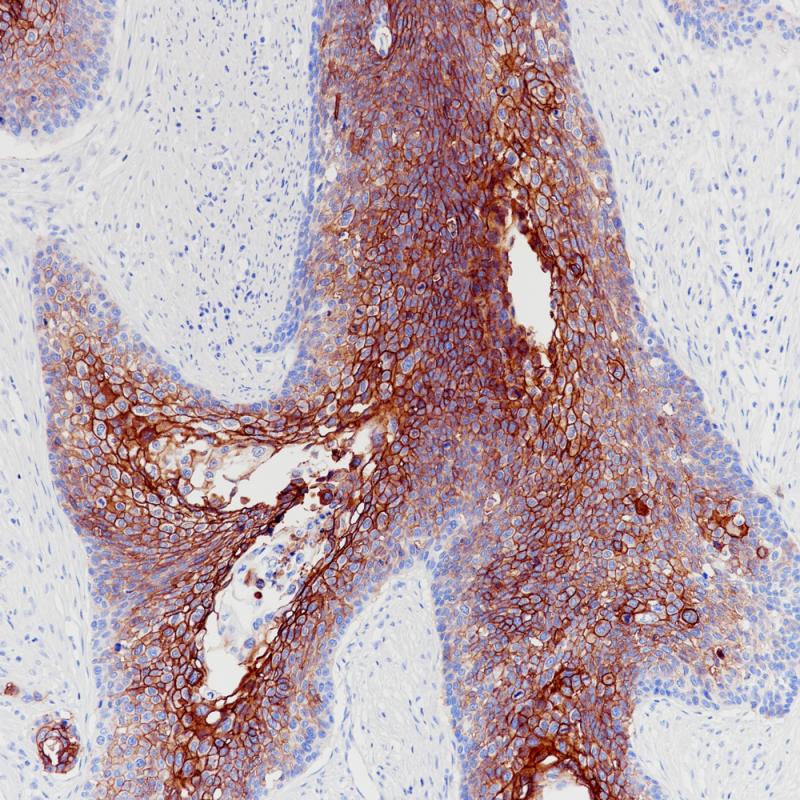

肺鳞癌TROP-2(BP6208)染色

食管癌TROP-2(BP6208)染色

TROP-2

重组兔单克隆抗体

TROP-2或肿瘤相关钙信号转导器2,也称为上皮糖蛋白-1抗原(EGP-1),是一种由TACSTD2基因编码的蛋白。这一跨膜糖蛋白在多种细胞信号通路中发挥作用,并首次被证实为细胞内钙信号的转化器。TROP-2在多种上皮组织和TROP2来源的肿瘤组织中表达,如扁桃体、食道、胰腺、前列腺和胃癌。另外,它也在阴性乳腺癌、非小细胞肺癌、尿路上皮癌和各种类型的实体瘤中均有高表达。TROP-2已成为研究人员开发抗体偶联药物的新靶点。

阳性对照

肺鳞癌

细胞膜